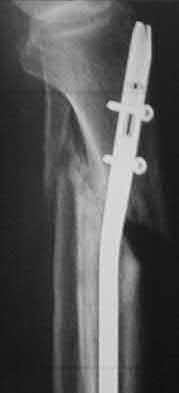

1. # A 32-year-old male sustains the injury shown in Figure A and undergoes treatment as shown in Figure B. Following placement of this implant, what is the best technique to confirm it is not too proud proximally?

The safe zone for tibial nail placement as seen on radiographs is just medial to the lateral tibial spine on the anteroposterior radiograph and immediately adjacent and anterior to the articular surface as visualized on the lateral radiograph.

Tornetta et al specifically located the safe zone for nail entry in a study using fresh frozen cadaver knees. The authors found that the safe zone for nail placement is located 9.1+/-5 millimeters lateral to the midline of the plateau and three millimeters lateral to the center of the tibial tubercle. The width of the safe zone averaged 22.9 millimeters and was as narrow as 12.6 millimeters.

The starting point of the of the nail can be best viewed on the lateral knee radiograph, an example of which is shown in Illustration A. Illustration B shows the "sweet spot" for nail insertion as defined by Tornetta.